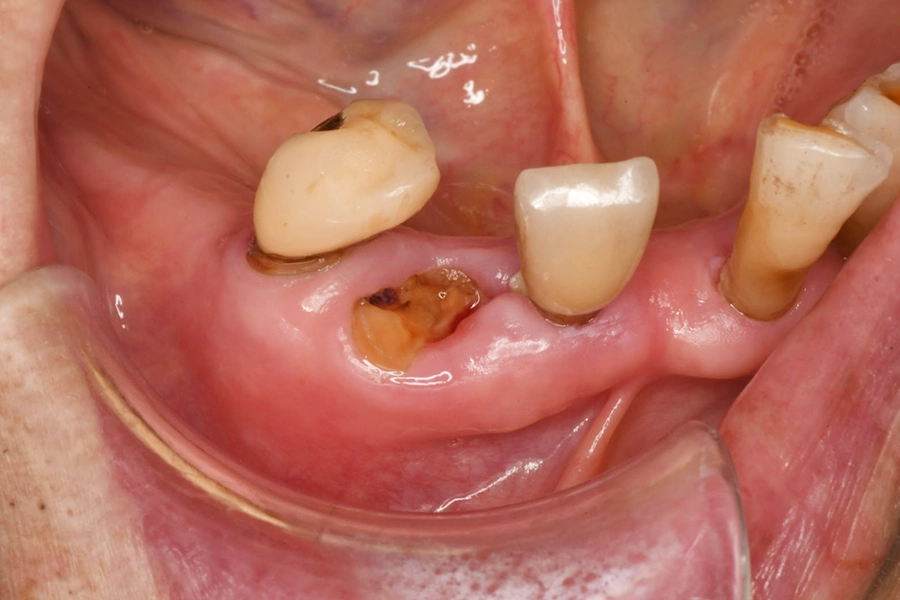

治療中の様子

歯冠部分に限局した歯の破折

破折片の除去